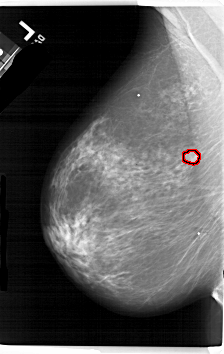

A_1657_1.LEFT_CC

LEFT_CC LINES 6691 PIXELS_PER_LINE 3856 BITS_PER_PIXEL 12 RESOLUTION 43.5 OVERLAY

FILE: A_1657_1.LEFT_CC.OVERLAY

TOTAL_ABNORMALITIES 1

ABNORMALITY 1

LESION_TYPE MASS SHAPE LOBULATED MARGINS OBSCURED

ASSESSMENT 4

SUBTLETY 3

PATHOLOGY MALIGNANT

TOTAL_OUTLINES 1

BOUNDARY